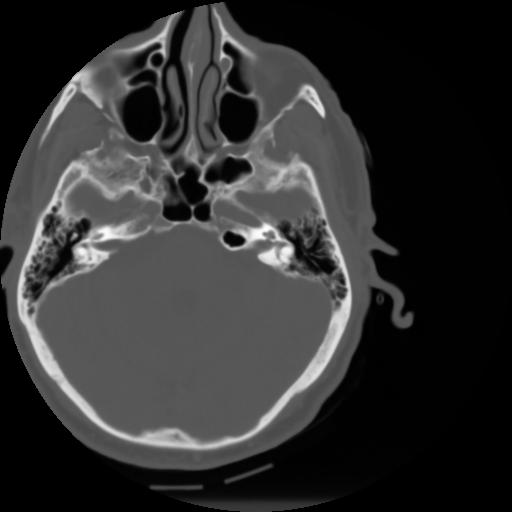

3 CEREBRO,,Axial,3.0,CEREBRO,,